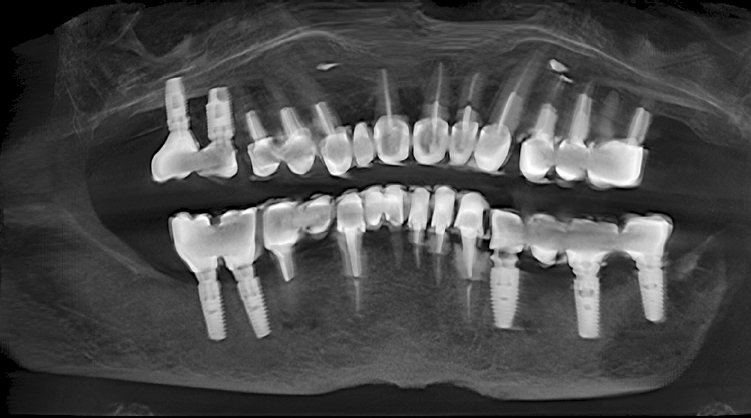

Computed tomography (CT) of the mandibles (Fig. 1), CT of the TMJ (Fig. 2), electromyography of the mandibular muscles (Fig. 3), and sonography of the TMJ (Fig. 4) were performed for diagnostic purposes.

Fig. 1. Pretreatment computed tomography of the jaws of patient K., 69 years old

Рис. 1. Компьютерная томограмма челюстей пациентки К., 69 лет, до лечения

The CT of the TMJ revealed that the head of the mandible was displaced distally on the right side. The mandibular heads were deformed on both sides. Electromyography revealed increased tone of temporal and bicuspid muscles at the existing position of the mandible. Sonography revealed the presence of clicks on the right and left TMJ regions when opening and closing of the mouth. The preliminary diagnosis was confirmed based on the diagnostic measures.